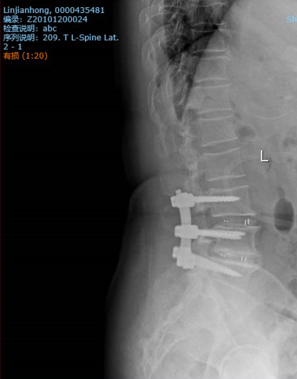

内固定手术是脊柱手术的一种泛指,通常表示对于患有腰椎间突出症、腰椎管狭窄症、腰椎滑脱症等疾病的患者,通过术中进行相应神经、脊髓减压,椎间盘摘除以后,通过外来器械钉棒系统及融合器,进行减压后脊柱的固定和融合,目的在于恢复手术后脊柱的稳定及功能,加快术后康复等。

脊柱内固定材料包括钉棒和融合器等

脊柱融合顾名思义,就是将上、下两个椎体“融合”为一个椎体的过程,通常是由于患者“生病”的椎间盘、上下异常活动的椎体压迫周围神经、脊髓,手术医生将“生病”的锥间盘取出,固定椎体,消除椎体活动度,然后在取出椎间盘的地方放入一个内固定器械“融合器”,目的在于“替代”原有的被手术去除的椎间盘的手术方式。而绝大部分腰椎间盘突出症、腰椎管狭窄症、腰椎滑脱症的患者均需要接受此类手术方式,而此类手术方式的重中之重就是融合椎体,而骨质疏松患者,通常会影响“融合”过程的进行,降低手术的疗效,故对于患有骨质疏松症的患者,术后抗骨质疏松至关重要!

远期并发症,包括钉棒的断裂、螺钉的松动、融合器的脱落、融合率的下降、融合时间的延长、临锥病的发生等,都是和骨质疏松症脱不了干系的,那么这些远期并发症都是什么意思呢?这里简单做一个科普,脊柱手术后的骨质疏松患者,由于骨量的低下、骨修复速度的缓慢、骨丢失速度的加快等原因,手术中打入骨头的内固定器械,往往不能很牢靠地被新生长的骨包裹,从而在骨头中的钉棒,在椎间隙中的融合器不能很好的被固定,随着时间的推移,患者的活动等,导致钉棒、融合逐渐后退,松动的过程。